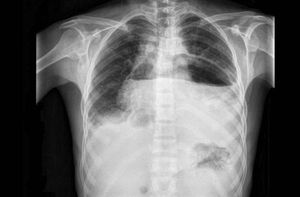

A 37-year-old man on regular haemodialysis for end-stage renal disease presented with progressive dyspnoea and orthopnoea 4 days after nephrectomy to control hypertension. What is the cause of this abnormal chest radiograph? 1) Gastric torsion 2) Achalasia 3) Pneumopericardium 4) Hiatal hernia